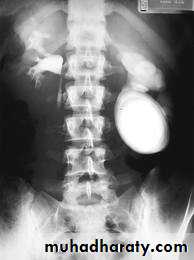

-Plain film may be useful in demonstrating calculi.

• Ddgx of stone on KUB :

• 1. Gall stone

• 2. calfied LN , cartilage ,fibroid,

• 3. Phlebolith: round, lucent centre.

Calcification is most important feature, mainly in bladder & lower ureters , but may involve whole ureters .